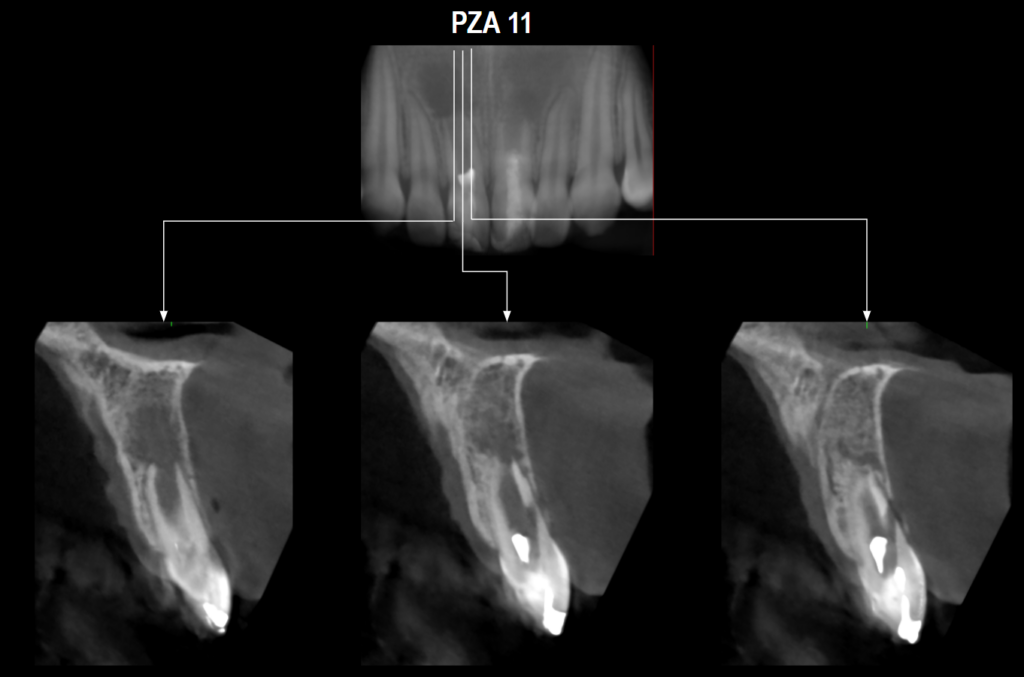

En la tomografía computarizada de haz cónico (CBCT) de campo reducido, evaluada en cortes axiales (Figura 2), coronales (Figura 3) y transaxiales (Figuras 4 y 5), se observa formación radicular incompleta, caracterizada por un conducto radicular amplio en los tercios medio y apical, así como un foramen apical de gran diámetro, asociado a un proceso osteolítico periapical difuso.

Adicionalmente, en la pieza 11 se identifica una imagen hipodensa de morfología tubular que se extiende desde el tercio cervical radicular hasta la superficie vestibular, provocando la pérdida de continuidad de la pared radicular, compatible con una perforación radicular iatrogénica. Se observa también pérdida de continuidad de la corona protésica, presencia de espigo-muñón y obturación

endodóntica del conducto.

CORTES TRANSAXIALES